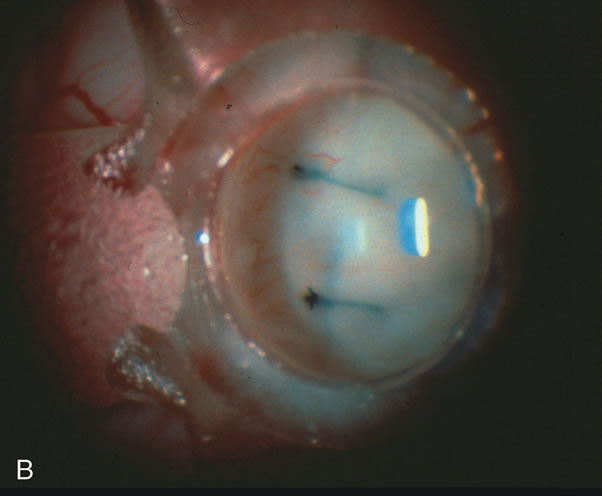

Fig. 1. The anatomic advantage of small incision cataract surgery for the glaucoma patient. A. Long-term bleb function with a large cataract incision is difficult to achieve with either ECCE-trabeculectomy or trabeculectomy followed later by ECCE. This bleb failed to form sufficiently when combined with large incision ECCE. The inflammation, bleeding, and long-term wound healing with stimulation of fibroblasts associated with this technique are more likely to cause bleb failure. In addition, the increased iris manipulation necessary to deliver the nucleus and subsequent iris repair adds to the long-term breakdown of the blood aqueous barrier. B and C. Two-site phacotrabeculectomy has the advantage of small incision cataract surgery combined with separate site trabeculectomy. The incision size is one third the size of the standard ECCE. The inflammation is less severe, and cataract wound healing is confined to the temporal area. Visual rehabilitation with phacoemulsification and foldable IOL is much faster. Phacoemulsification allows successful lens extraction even in the unfriendly environment of a smaller pupil compared with ECCE. The trabeculectomy is performed in an entirely different site, well away from the wound healing associated with temporal phacoemulsification. The likelihood of this filter functioning long-term is greater than with ECCE-trabeculectomy. D. The surgeon also has the option of single-site phacotrabeculectomy with foldable IOL. Both the lens extraction and trabeculectomy are performed through one small 3.5-mm limbal incision.